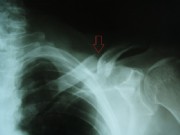

Acromioclavicular dislocation

(Acromioclavicularluxation)

By falling on the arm, the joint capsule of the so-called acromio clavicular joint (between acromion and clavicle) tear, and the clavicle height, depending on the severity of the injury, moves more or less. Lower stages (called Tossy I and II) are not operated, but eventually stabilized with a shoulder brace.

The Tossy III is a complete dislocation (tearing of the capsule ligament entirely) and should at least be surgerically treated in case of younger patients. This is done with a plastic band loop, which is looped around the coracoid and which brings the clavicle back to its original position. This band is fixed by means of clamping screws.

The arrow points to the here already repositioned acromioclavicular.